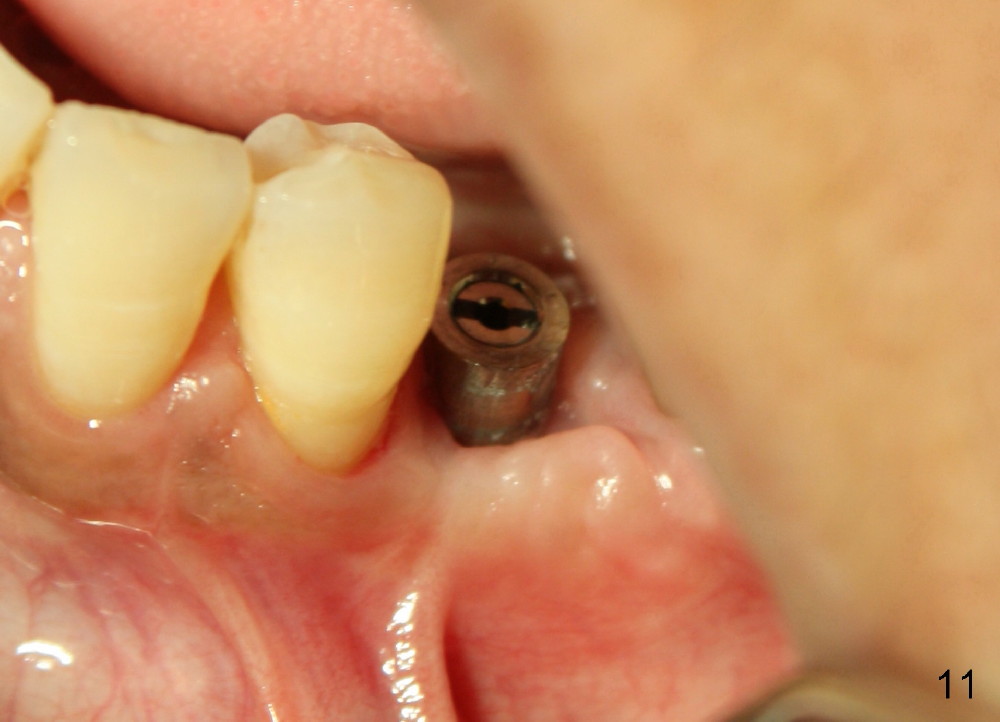

Twelve days post 2nd debridement, the wound does not heal normally. Out of desperation, Arestin is placed incompletely in the mesiobuccal pocket of #19. Fortunately, the wound heals at the site of #20 one month later (Fig.11). No infection is observed 4 months post 2nd debridement (Fig.12,13). Eventually the tooth #19 becomes symptomatic. Extraction and immediate implant is planned. In case the implant at the site of #20 fails, a cantilever bridge is fabricated using the posterior 2 implants.